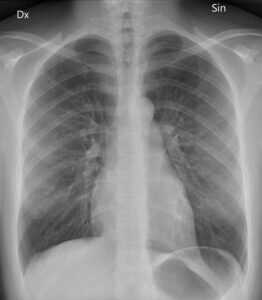

| 6 | Lung & Chest Imaging | Distinguishes air, fluid, and tissue to detect infections or masses | X-ray, CT |